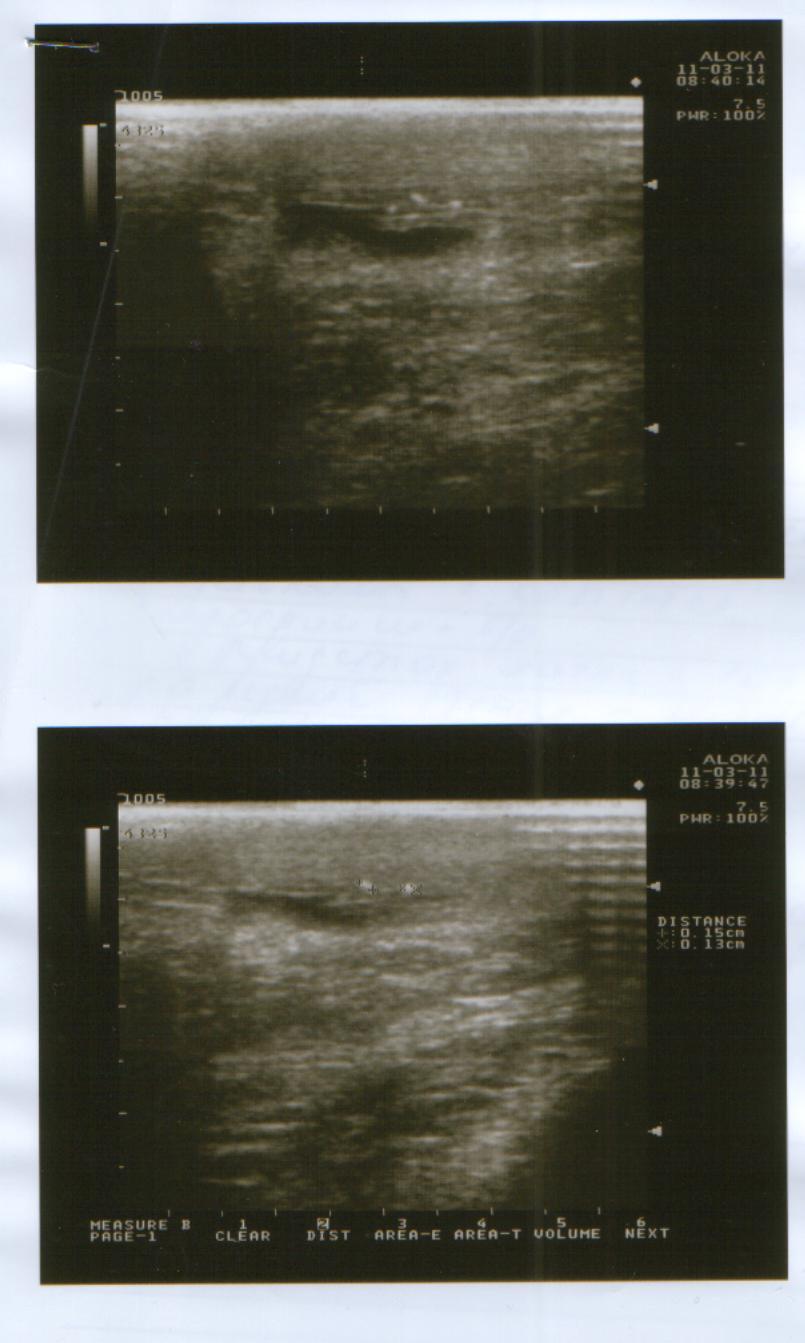

Сегодня(11.03.2011 г.)я ходил на приём к урологу.После осмотра он направил меня на УЗИ мошонки,простаты,мочевого пузыря и почек.УЗИ мошонки показало,что левое яичко действительно сжалось и почти в три раза меньше правого.Уролог сказал,что скорее всего,летняя операция грыжесечения и нынешняя проблема связаны и поставил мне диагноз "Атрофия левого яичка".А,да.УЗИ остальных органов показали,что всё остальное в порядке.Туберкулёза у меня не было и контактов с больными им тоже не было.

Снимки УЗИ и заключение уролога в прикреплённом архиве